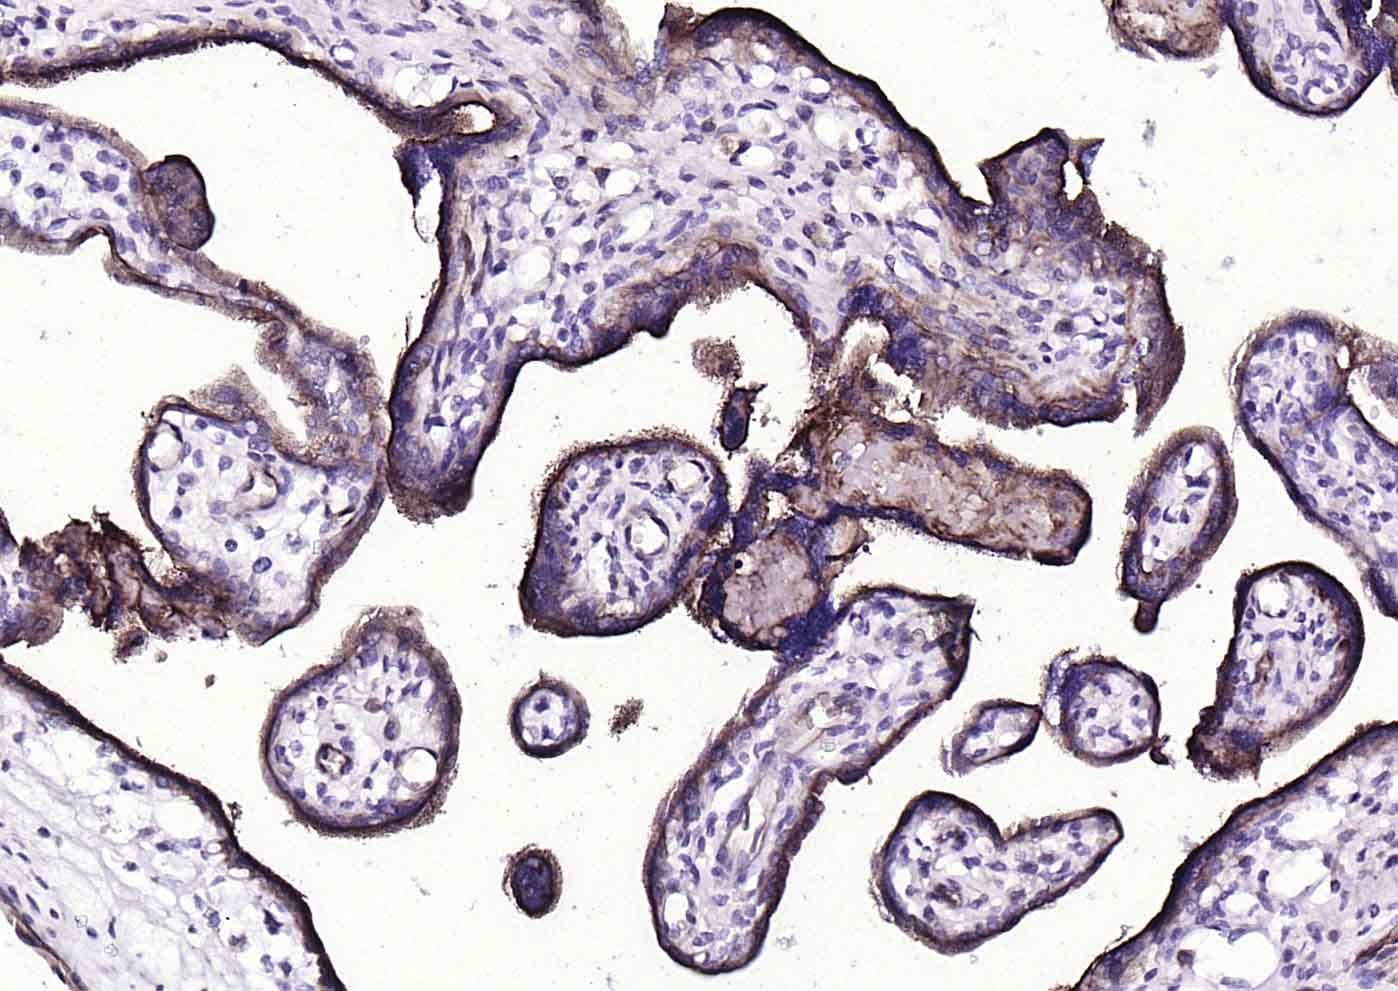

Paraformaldehyde-fixed, paraffin embedded (human placenta); Antigen retrieval by boiling in sodium citrate buffer (pH6.0) for 15min; Block endogenous peroxidase by 3% hydrogen peroxide for 20 minutes; Blocking buffer (normal goat serum) at 37°C for 30min; Incubation with (CD39/ENTPD1) Monoclonal Antibody, Unconjugated (bsm-54043R) at 1:200 overnight at 4°C, followed by operating according to SP Kit(Rabbit) (sp-0023) instructionsand DAB staining.